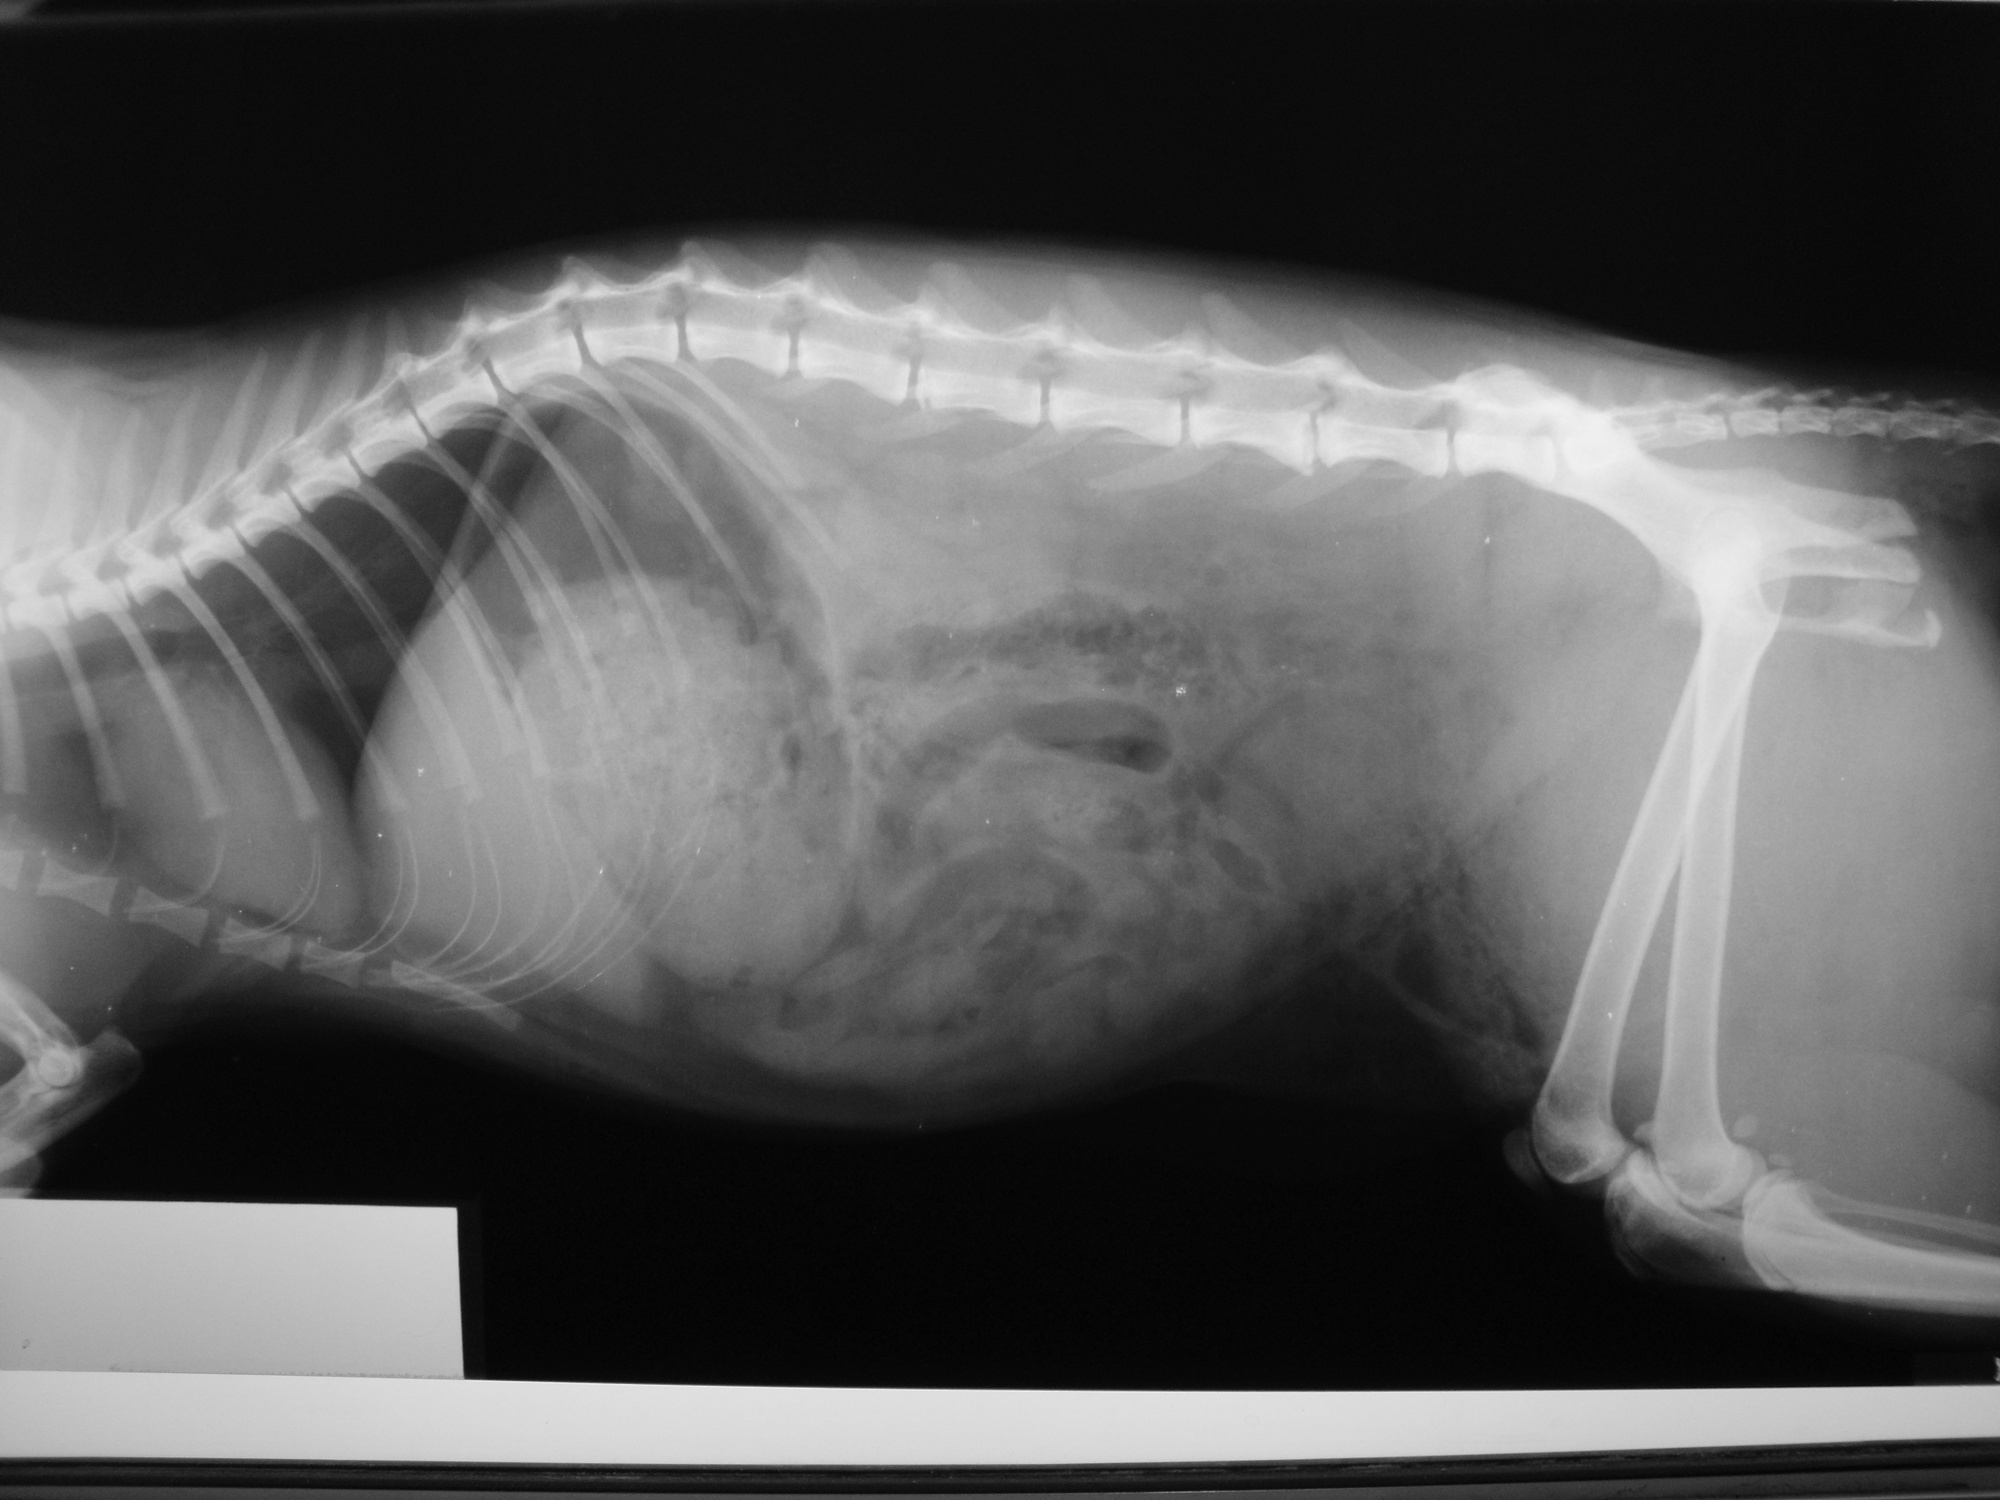

主題: 民族路被車壓過的黑貓 申請者姓名: 劉素鳳 花色: 申請日期: 2013-08-18 02:20:32 申請者部落格: 申請者臉書網址: 所在縣市/合作醫院: 高雄市/樂生動物醫院 治療費用: 3500元 需求人數: 8人 已結案 (2013-09-03 16:24:09) 報名人員: aki(已付款)、Fatefaye Wu(已付款)、楊政遠(已付款)、Wasca(已付款)、maiwu(已付款)、sally x3(已付款)、 候補人員: 動物病情說明: 這是在TNR貓途中結束後在民族路上發現的車禍貓, 當時貓躺在路邊抽動, 因為時間已經很晚緊急打電話給樂生動物醫院, 醫生將貓咪仔細檢查發現是車禍貓咪,後軀癱瘓無痛覺反應,經X光檢查,脊椎受傷(第3及第5腰椎),腸薦關節脫臼及骨盆骨折,腹部皮下氣腫及出血,點滴住院後,貓咪還是上天堂去了, 送了他一程, 感謝大家善心捐款.

6.X光檢驗 300*2=600

total 3500急救後貓後來當天使去了. 醫生發現貓是被碾過.